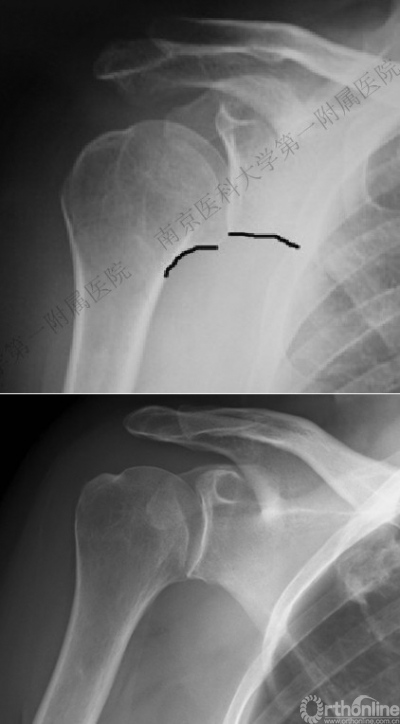

四、分型

肩关节后脱位:

Ⅰ型: +肱骨颈骨折。

Ⅱ型: +肱骨颈骨折+小结节骨折(病例3)。

Ⅲ型: +肱骨颈骨折+小结节骨折+大结节骨折(病例2),以骨折线向肱骨近端外侧壁延伸为另一特征。

五、反Hill-Sachs 损伤对肩关节稳定性的影响